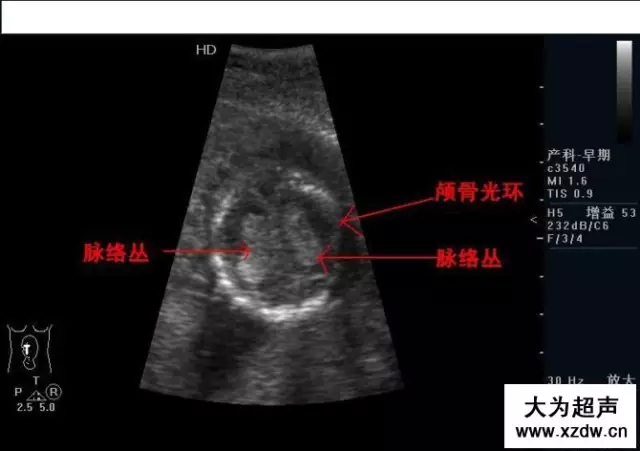

產科超聲正常圖片